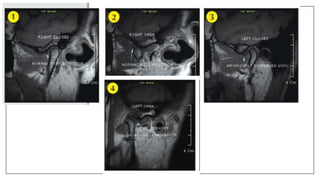

RF coils forTMJ imaging